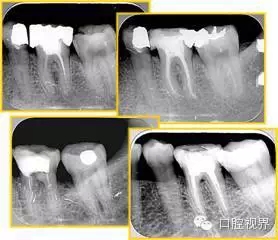

6. 鈣化

常見有修復(fù)性鈣化和增齡性鈣化。下面為根管鈣化 X 線片。

7. 器械折斷

右圖及下圖為器械折斷的 X 線片。箭頭處示折斷器械。

解決方法: ( 1 )取出。 ( 2 )通過。 ( 3 )重新確定工作長度,充填。 ( 4 )根尖手術(shù)。

器械折斷可以不用取出,取出的原因多是患者心理因素。留在里面的器械關(guān)鍵是進(jìn)行消毒,預(yù)防性使用抗感染藥物,預(yù)防感染。